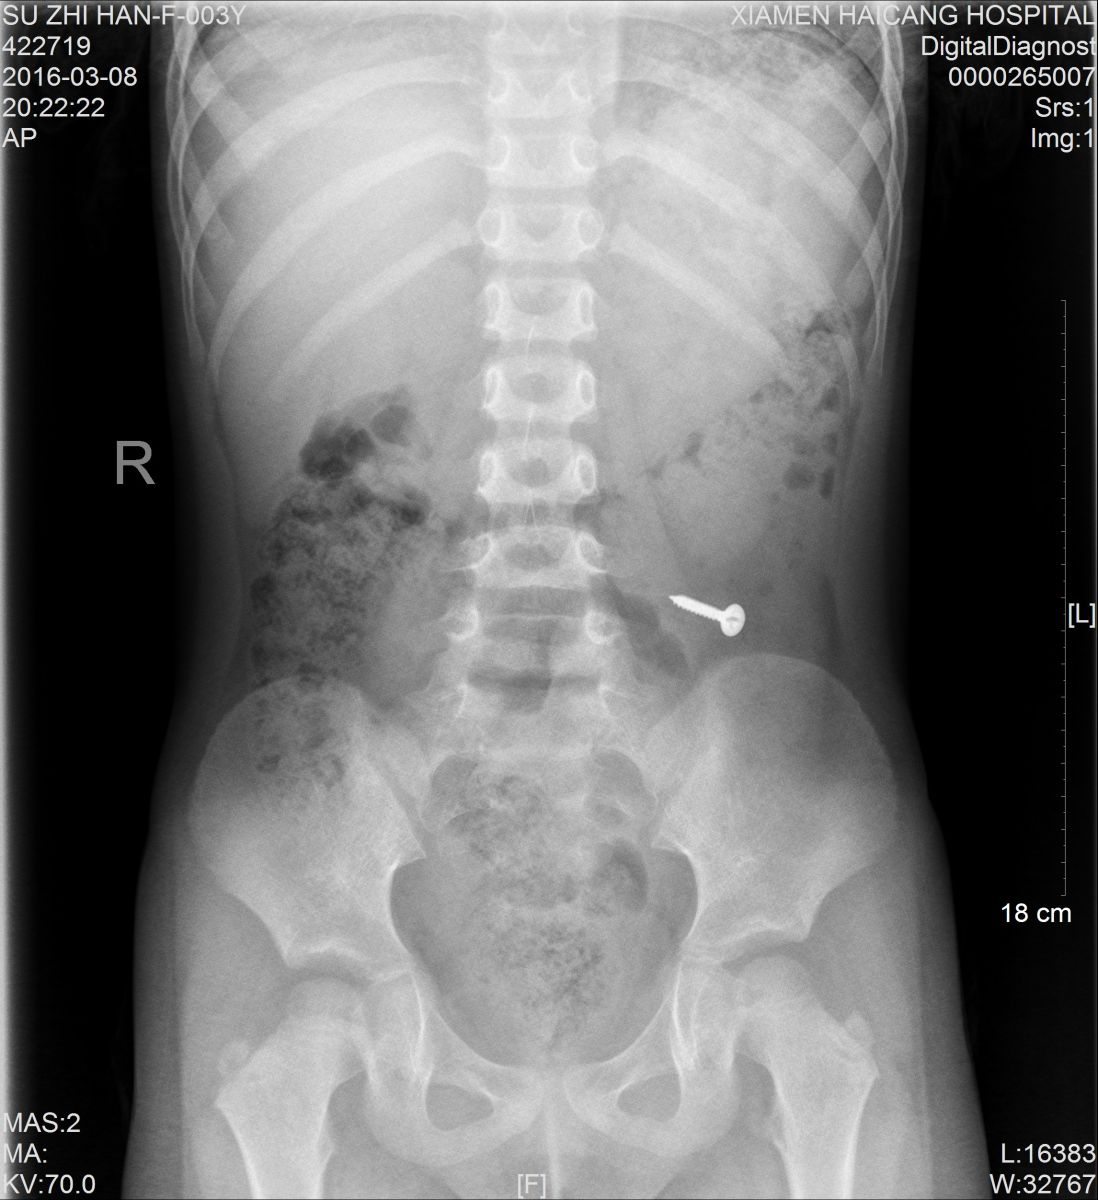

值班的医生了解情况后,马上安排小桐做X光片检查,检查影像一出来,大家都吓了一跳,只见小桐身体里清晰地躺着一个金属异物,经与小桐再三辨认,确定是一颗螺丝钉。确诊后,医生马上安排小桐转诊小儿外科治疗。

据医生介绍,由于患者年龄太小,手术损伤大,目前没有腹痛、腹膜炎等肠穿孔征象,螺丝钉不是很大,有可能自行排出,便建议随访,让患儿多吃些富含纤维素的食物,如韭菜、芹菜,以促进消化道蠕动,加速螺丝钉的排出。同时告知小桐父母需密切观察大便中是否有钉子排出,如有呕血、腹痛、发烧等异常情况,需马上就医。

3天后,小桐再来金沙集团 拍片复查,发现螺丝钉已经顺利排出,这才让父母放心。